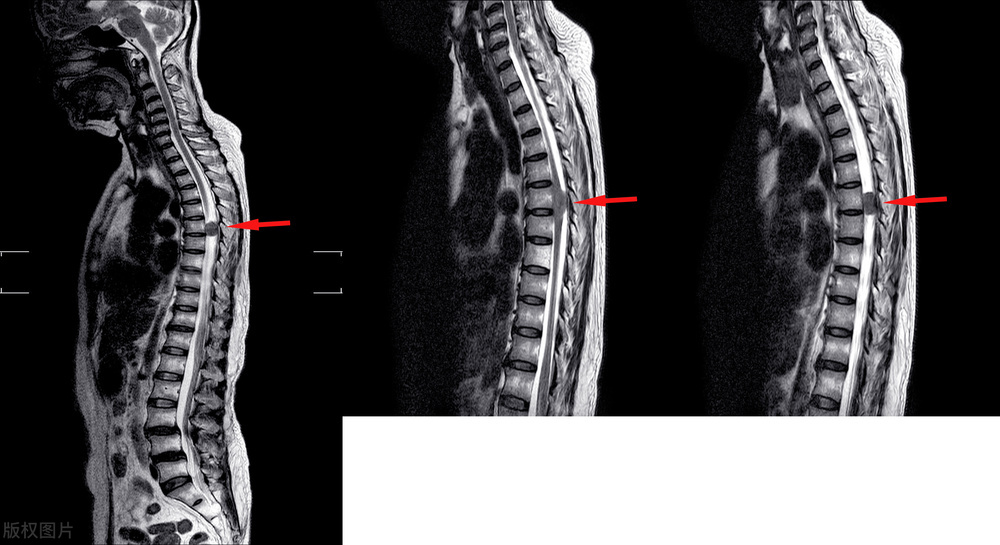

一 位 4 8 岁男性患者,检查出 腰 4- 5 椎间盘膨出,问诊时说自己主要就是腰痛,有时候臀部和大腿有点不舒服,其他没有啥症状。